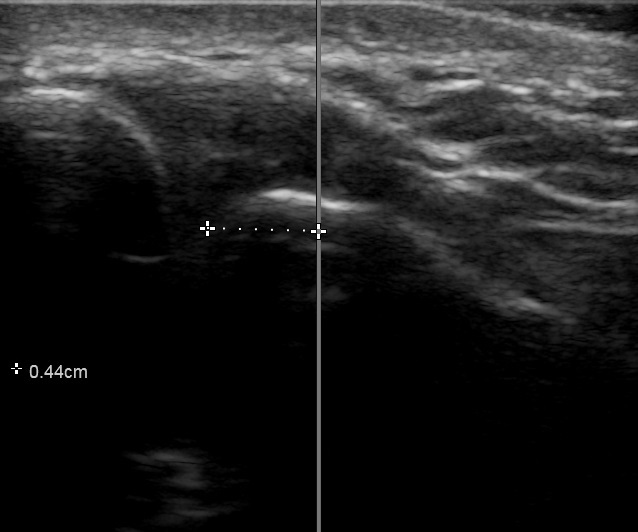

The width of the AC joint normally measures 1-6mm in females and 1-7mm in males. A joint width of <0.5mm may be considered normal in patients over 60 years old.5 The joint plane is typically slanted 20°–30°, with the clavicle overriding the acromion, however, there is significant variability in the degree of slant, ranging from nearly vertical to nearly horizontal.6 The small size of this joint makes it relatively difficult to access in one pass using a palpation-guided approach, which relies on landmark palpation. The act of walking the needle along the clavicle or acromion until it falls into the joint is painful for the patient. Moreover, there is no guarantee that the injectate is truly in the joint space using the palpation-guided approach.

Two Primary Care Sports Medicine (PCSM) Fellows who were trained in musculoskeletal anatomy and musculoskeletal ultrasound, served as the study investigators. They were supervised by a board certified PCSM Attending Physician who is also credentialled and Registered in Musculoskeletal (RMSK) sonography. One of the study investigators was asked to identify the patient’s left and right AC joint using the palpation technique and then using a pen, mark the site through which they would insert the needle. The second PCSM Fellow then centered a Fujifilm Sonosite PX 15-4 ultrasound probe over the pen mark. The distance to the nearest border of the AC joint was measured and recorded using the ‘caliper’ function in the Sonosite software to the nearest tenth of a millimeter. The investigator’s accuracy on each shoulder was not made available to them, so there was no opportunity to adapt their approach to future subjects. One Fellow marked both shoulders of a single subject while the second Fellow only operated the POCUS on that subject.

Across all subjects, the raw mean distance from the point landmarked by the investigator compared to the nearest margin of the AC joint was 8.62mm (95% CI: (8.58-8.66)). Within-subject variation in the distance measured was minimal across shoulders (Figure 4), and neither age, gender, nor BMI had any association with the distance (p=0.373, p=0.842, p=0.431, respectively).

Our study demonstrated that on average, a skilled investigator typically landmarks a space 8.6mm away from the nearest border of the AC joint and is more likely to be medial than lateral. Laterality is important, too, because the angle the joint makes is inferior and medial. Using the palpation-guided technique, a “lucky” angle is less likely to be achieved if the investigator is medial to the joint. It is worth noting that the pain experienced by the nearly 60% of patients who reported an adverse event during an AC joint injection cannot be differentiated between pain from piercing the skin or missing the joint. However, using POCUS to directly visualize the joint and the angle it makes, this landmarking error is eliminated. With a slow, deliberate approach under ultrasound guidance, the needle can be advanced between the acromion and clavicle in one steady movement. In addition, direct visualization of the injectate filling the joint space all but ensures a successful procedure, while minimizing patient discomfort.

Notwithstanding the fact that the width of a 25ga (0.52mm) needle can be greater than a normal AC joint in an elderly patient (<0.5mm), the chances of ‘blindly’ inserting a needle into a space as small as the AC joint without some manipulation is very unlikely. Each repositioning of the needle during a palpation-guided injection causes additional patient discomfort.